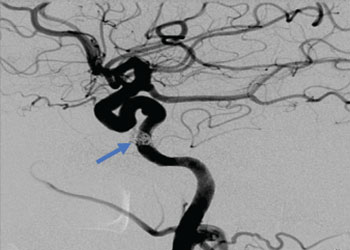

Endovascular:

Hydrocephalus and Brainstem Tumor

Author: Jonathan L. Brisman M.D., F.A.C.S., Read More!